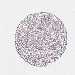

LIVER CANCER - Protein expressioni

A mouse-over function shows sample information and annotation data. Click on an image to view it in a full screen mode. Samples can be filtered based on level of antibody staining by selecting one or several of the following categories: high, medium, low and not detected. The assay and annotation is described here.

Note that samples used for immunohistochemistry by the Human Protein Atlas do not correspond to samples in the TCGA dataset.

Antibody stainingi

Antibody staining in the annotated cell types in the current human tissue is reported as not detected, low, medium, or high, based on conventional immunohistochemistry profiling in selected tissues. This score is based on the combination of the staining intensity and fraction of stained cells.

Each image is clickable and will lead to virtual microscopy that enables deeper exploration of all samples and also displays staining intensity scores, fraction scores and subcellular localization as well as patient and tissue information for each sample.

Antibody HPA060991

Antibody HPA063556

Antibody CAB017690

Staining

High

Medium

Low

Not detected

Intensity

Strong

Moderate

Weak

Negative

Quantity

>75%

75%-25%

<25%

None

Location

Nuclear

Cytoplasmic/membranous

Cytoplasmic/membranous,nuclear

Carcinoma, Hepatocellular, NOS

Cholangiocarcinoma